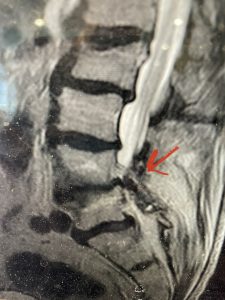

The next patient is a 71 year-old male with a two-year history of low back pain and lower extremity pain, numbness and weakness. His left leg was worse than the right. He had had five epidurals with no improvement. He also had tried physical therapy and medicines but nothing helped. He also felt that over the last three weeks he had gotten worse. He also had recently had some decreased sensation of bladder fullness and difficulty with bowel movements. MRI revealed a very tight L2-5 stenosis with an extruded L3-4 disc fragment (Fig 3).

(Figs 3a) Sagittal (a) and Axial (b) T2-weighted lumbar MRI demonstrating severe spinal stenosis L2-5 (arrow)and extruded disc at L3-4 on axial image (arrow)

He had concentric severe stenosis with severe compression of the lateral recess and foramen at L3-4 secondary to the superimposed disc herniation. The fact that he had gotten worse with subtle cauda equina features with an extremely tight canal, he underwent a decompressive laminectomy. We also augmented his laminectomy with an in situ fusion from L3-5 as he was relatively young, with more time to reform arthritis, and had been unstable enough to extrude a disc fragment. By placing “bone dust” or bone material along the sides of the spine, specifically laying it across the transverse processes after they have been drilled to bleeding bone, you provide an environment where bone formation is induced to connect the segments, stabilize them, and thereby reduce the signal to make more arthritis as that signal is still present despite the laminectomy. What was interesting was that we encountered a large extruded disk fragment that was significantly contributing to his compression which is often not found in patients in this age bracket. Post operatively he had much improvement of leg pain.